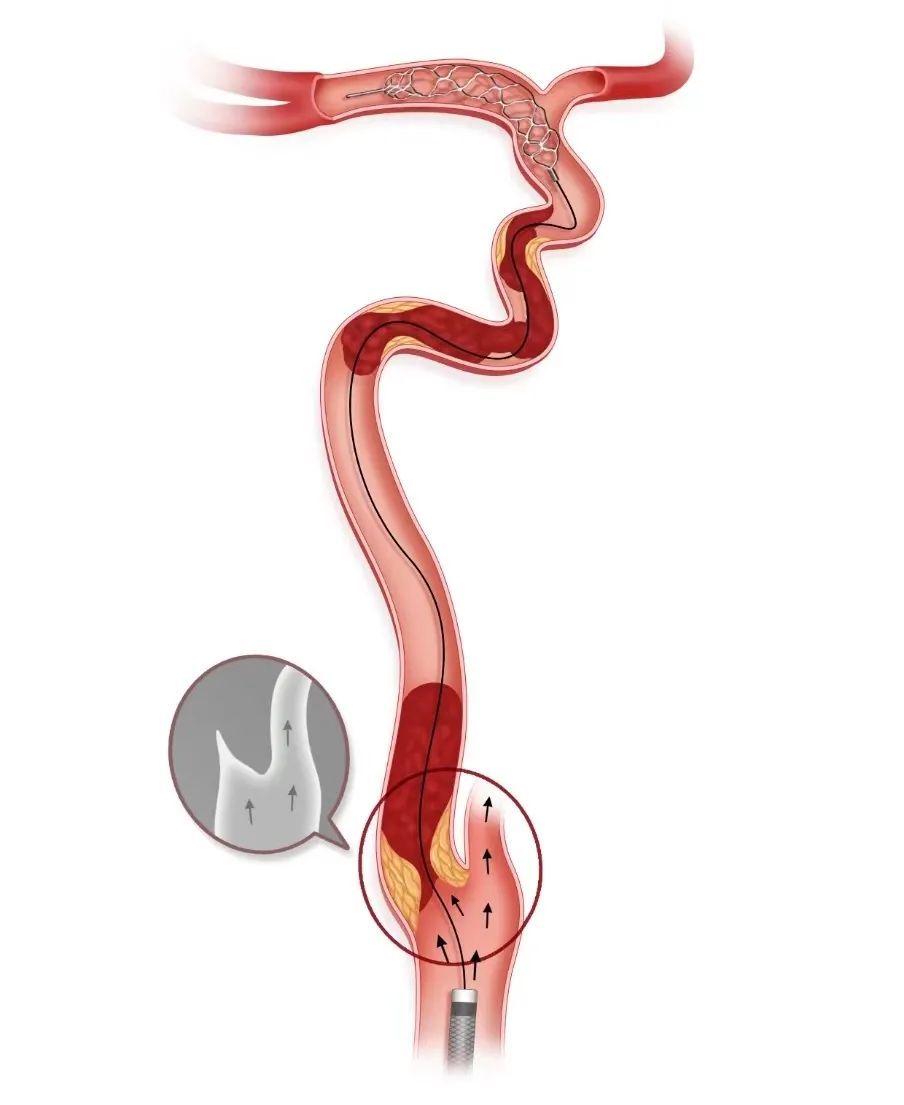

步骤四

Tethys AS®血栓抽吸导管反复抽吸清理血栓

持续负压下前进Tethys AS®血栓抽吸导管,反复抽吸,清理闭塞管腔内的血栓。如果造影发现Syphonet®取栓支架内捕获了脱落的血栓,则回撤Syphonet®取栓支架,清理支架内血栓。